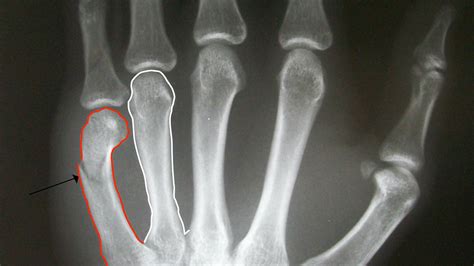

X-ray Photos of Bone Fracture Patients Stock Image - Image of finger ...

1600×1146

Hand Fracture - Raleigh Hand Surgery — Joseph J. Schreiber, MD

1953×1500

An x-ray showing a fracture of the 3rd and 4th metacarpal bones in the ...

1300×1152